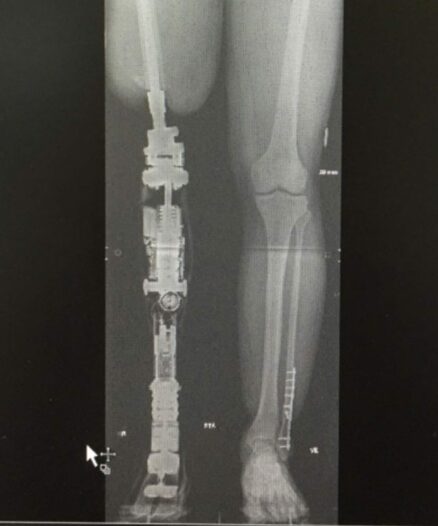

I 2010 begyndte Aarhus Universitetshospital (AUH) - som de eneste i Danmark - at lave osseointegration. Her bliver en titaniumskrue eller titaniumstav indopereret i knoglen.

Når den er vokser helt fast i knoglen, laver vi - i tæt samarbejde med AUH - proteserne til osseointegration.

Faktisk har vi i 2022 lavet proteser med elektriske knæled til den første dobbelte osseointegration i Danmark - og blandt de første dobbelte på verdensplan.

Herunder kan du se, da veteranen Jesper med dobbelt osseointegration tog de første skridt med sine nye benproteser med elektriske knæled.

Se veteranen Jesper med den første dobbelte osseointegration, da han tager de første skridt med benproteser med elektriske knæled i Danmark!